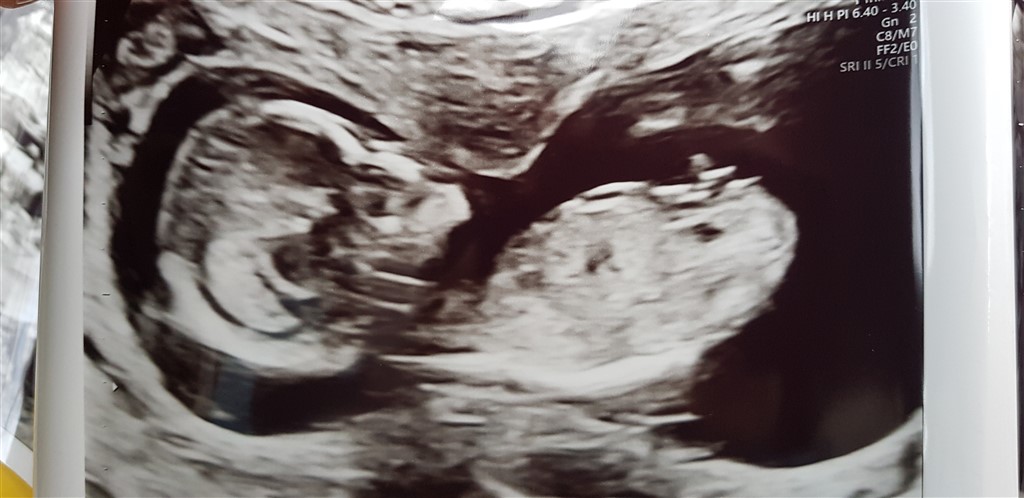

Jeg har fået bud på både dreng og pige. Hva siger i? Billede taget 13+2

Vedhæftede fotos (klik for at se i fuld størrelse)